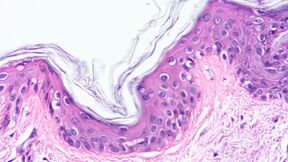

Microscope image of wavy skin tissue layer, pink and purple cells forming dense clusters

Bioengineering human tissue: Design, fabrication, analysis BIP, is an international course in human tissue engineering held both online and in-person, at TU Darmstadt, Germany.

During the course, students will learn about 3D tissue design, transport phenomena, mechanical conditioning, and challenges in clinical applications. Students will also gain hands-on experience with state-of-the-art methods for creating and analysing 3D human tissue models.